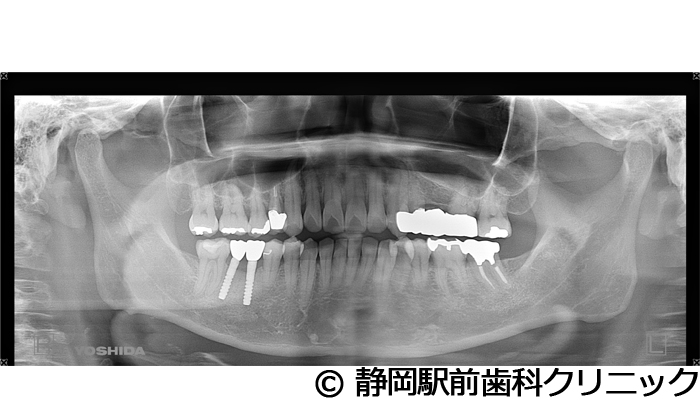

【症例4】全顎的インプラントとセラミックによる審美補綴

- 治療前

- 治療後

- 治療名

- 全顎的インプラントとセラミックによる審美補綴

- 費用

- 1,200,000円(税込)

- 期間

- 1年3ヵ月

治療内容

患者様の症状

左上ブリッジが歯根破折してしまい、他院で入れ歯を作ったが使い心地がよくないため、インプラント治療希望。

治療方法

抜歯後、骨治癒後にCTを撮影して、綿密に治療計画を立てた。上顎洞の距離やインプラント同士のバランスを熟慮し、インプラントを埋入した。全体的な噛み合わせの調整を重ねた後、人工歯を被せて咬合と見た目の回復を行った。

治療結果

入れ歯のような違和感が全くなく、力を入れてしっかり噛むことができるので、食事することが楽しくなったとご満足いただけました。見た目もセラミックの歯が入ったので、自分の歯が戻ったようだと喜んでいただきました。

※治療結果は個人差があります。

治療を行う上での注意点(リスク・副作用)

術後は、出血、腫れ、痛みなどが出る可能性があります。

【症例5】全顎的インプラントとセラミックによる審美補綴

- 1,800,000円(税込)

- 1年6ヵ月

全体的に歯がないため、噛めない。インプラント治療希望。

全体的に残根は抜歯を行い、術前にCTを撮影し緻密に治療計画を立てた。インプラント埋入はブロックごとに行い、噛み合わせの調整を重ねた後、人工歯を被せて咬合と審美の回復を行いました。

しっかり奥歯で食べ物を噛み切ることができるようになり、何でも食べることができるようになったと喜んでいただくことができました。口元を気にせずに笑うこともできるようになり、見た目もキレイになったとご満足いただけました。